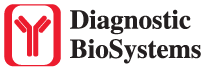

This kit stains strongly sulfated mucosubstances. Strongly sulfated mucosub-stances stain blue in paraffin tissue sections, while the nuclei stain pink to red and the cytoplasm and background stain pale pink.